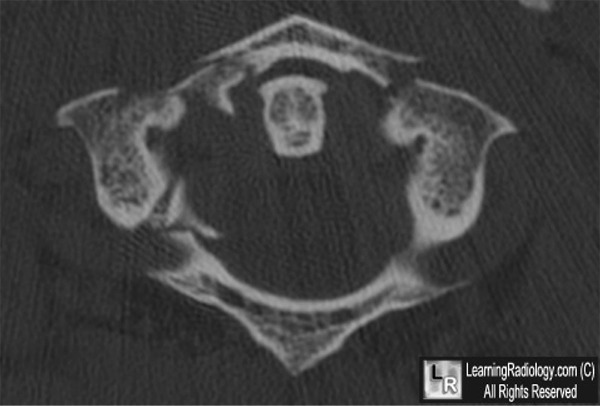

Jefferson fracture

Blow out fracture of the atlas caused by axial loading.

Best visualised with a peg view on plain radiography.

Unstable injuries requiring careful specialist spinal input